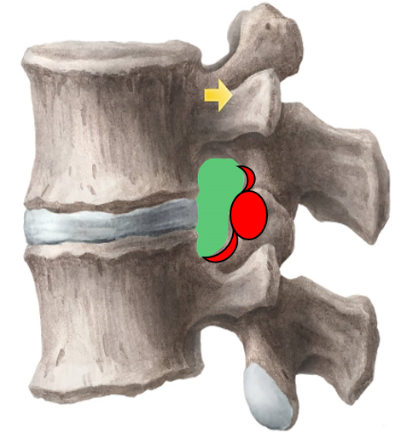

为解决以上问题���,我们提出“椎间孔镜按需成型5级法”��,即将椎间孔镜术中椎间孔成型的实际操作范围进行分级���:0级����:不成型����,见图 1��;1级���:软组织成型�����,只去除关节囊等部分软组织�����,基本不做骨性成型���,见图 2���;2级�����:少许骨质成型���,但不显露下关节突关节面����,见图 3����。3级成型�����:上关节突尖部或上1/2去除成型���,显露下关节突关节面���,见图 4�����;4级成型����:上关节突大部分成型或伴有部分椎弓����、峡部或下关节突小部分���,但预留基底部一部分��,见图 5��。

图 1 0级成型 |

图 2 1级成型 |

图 3 2级成型 |

图 4 3级成型 |

图 5 4级成型 |